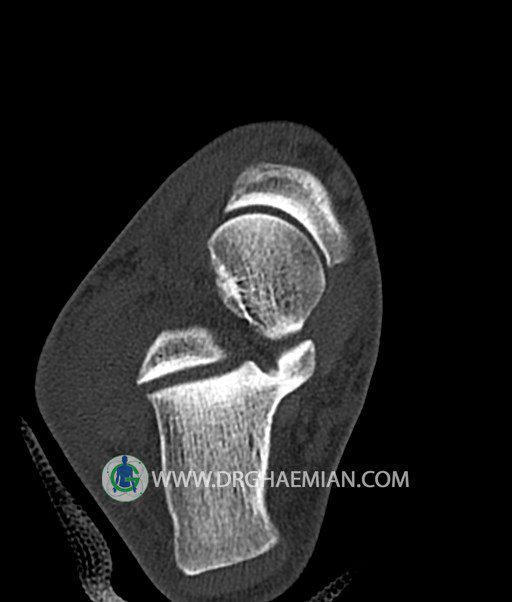

سی تی اسکن پا تصاویری عرضی از پا ایجاد می کند. این روش تصویربرداری از اشعه ایکس برای ایجاد تصاویر ایجاد می شود. در این کیس هيپرپلازي مچ پا، تورم نسج نرم و استئوفیت در مچ پا بیمار مشاهده می شود.

سي تي اسکن مچ پاي راست (مولتي ديدکتور 16 با مقاطع ظريف و بازسازي هاي ساژيتال و کرونال و 3D):

– تورم نسج نرمي در اطراف قوزک خارجي پاي راست

– Cortical Fx در قسمت خلفي اپيفيز ديستال تيبيا و

– هيپرپلازي lateral tubercle در تالوس ( stieda process ) همراه با اوستئوفيت در لبه

مديال تيبيا و تالوس